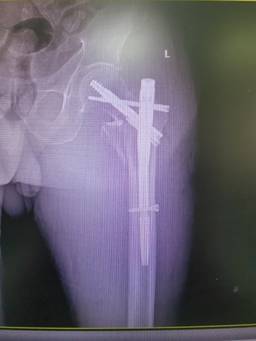

無(wú)獨(dú)有偶,石化醫(yī)院骨科隨后又收治了一位78歲左股骨轉(zhuǎn)子間骨折患者,團(tuán)隊(duì)再次自主完成高齡股骨轉(zhuǎn)子間骨折PFBN固定術(shù),術(shù)后患者恢復(fù)良好。

面對(duì)“人生最后一次骨折”,現(xiàn)在患者有了更好的選擇。據(jù)了解,目前PFBN技術(shù)在國(guó)內(nèi)開(kāi)展屈指可數(shù)。此次石化醫(yī)院骨科2例手術(shù)的成功,填補(bǔ)了本地區(qū)該項(xiàng)技術(shù)的空白,也標(biāo)志著科室在老年髖部骨折微創(chuàng)手術(shù)領(lǐng)域又邁入了一個(gè)新的臺(tái)階。